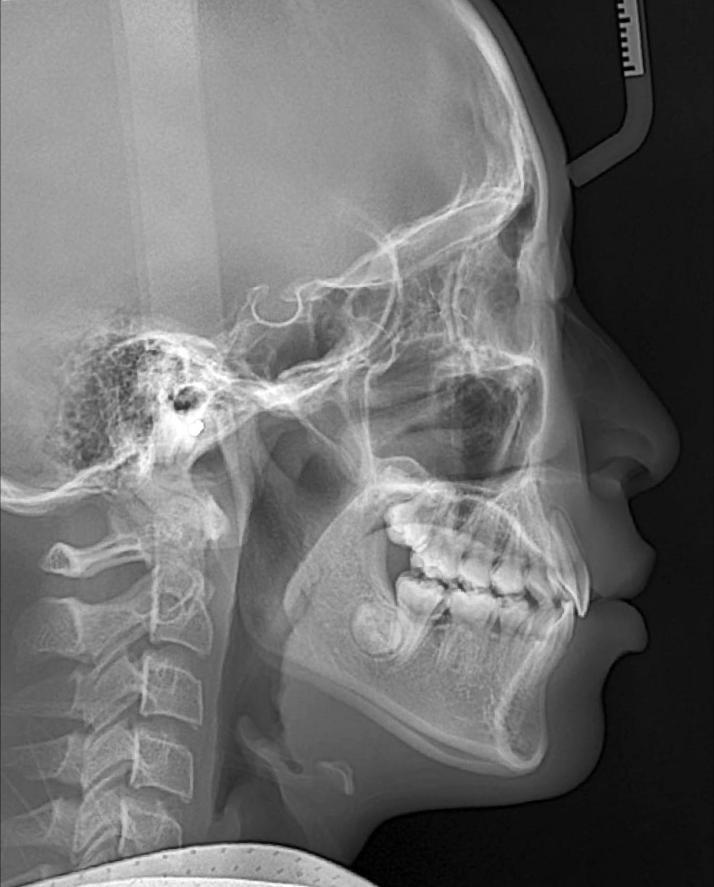

这位小朋友主诉牙不齐,嘴突,没下巴,来面诊时刚刚结束替牙期,正处于年轻恒牙列,生长发育高峰期。

根据牙片资料和口内检查发现骨性,上前牙唇倾,lll度深覆盖,上下颌牙弓狭窄,右下4左下5先天缺失,上颌轻度拥挤,下颌牙齿散在间隙,颏唇沟较深,闭唇时颏肌紧张。

从牙片资料看上下前牙内收直立,颌平面整平,上颌内收,前牙达到正常覆合覆盖,颏部前伸良好。